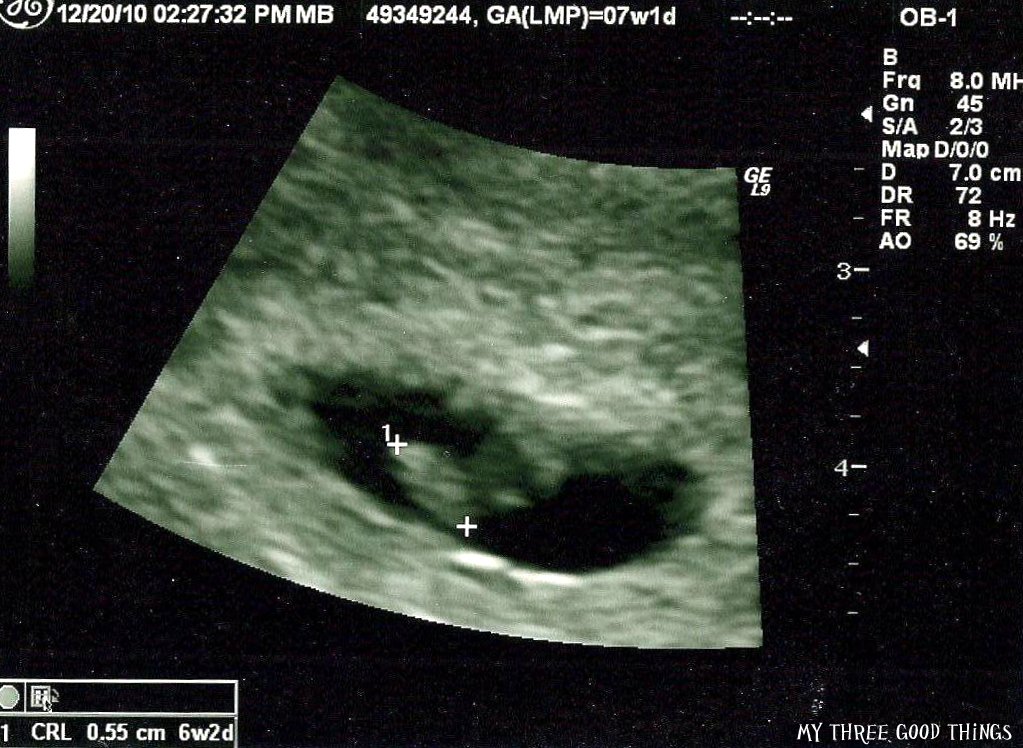

My Three Good Things Coping with Miscarriage What Do You See On Ultrasound After Miscarriage What happens after a miscarriage. He or she may also draw blood. This level is often repeated after 48 hours. At 10 to 14 weeks (often called the dating scan) and between 18 and 21 weeks. Most of the tissue passes within 2 to 4 hours after the cramping and bleeding start. A low or falling level of hcg could. What Do You See On Ultrasound After Miscarriage.